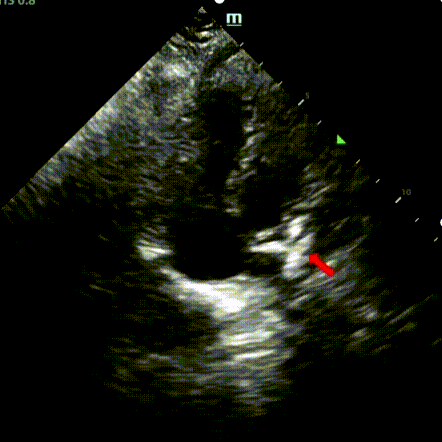

Um homem de 9 anos com ASD secundum (7,5-7,9mm) foi tratado usando um oclusor MemoSorb BDASD-I 12mm e sistema de entrega 12F. Não foram observadas complicações ou comorbidades pré-procedimento.

Serial echocardiographic follow-ups showed stable device position and favorable cardiac remodeling. Gradual degradation confirmed the occluder's long-term safety and efficacy.